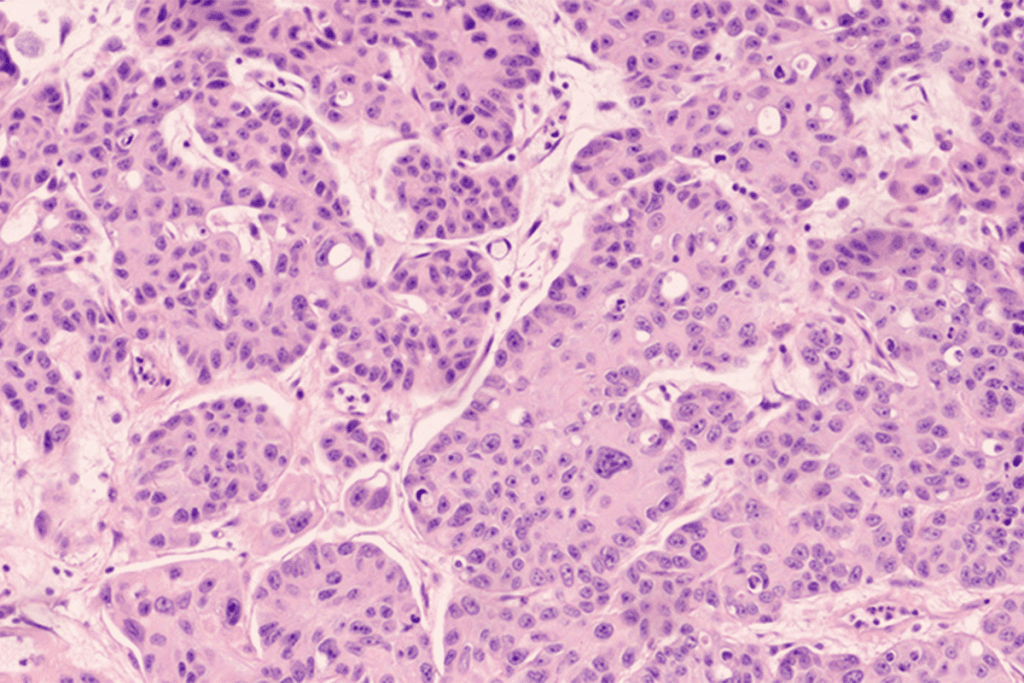

Types of Bladder Cancer

Bladder cancer types depend on the cells affected. The most common is urothelial carcinoma, starting in the bladder’s lining cells. Other types include squamous cell carcinoma and adenocarcinoma, each with its own treatment needs.

“The type of bladder cancer matters a lot for treatment,” a top urologist notes. Knowing the exact type is essential for a good treatment plan.